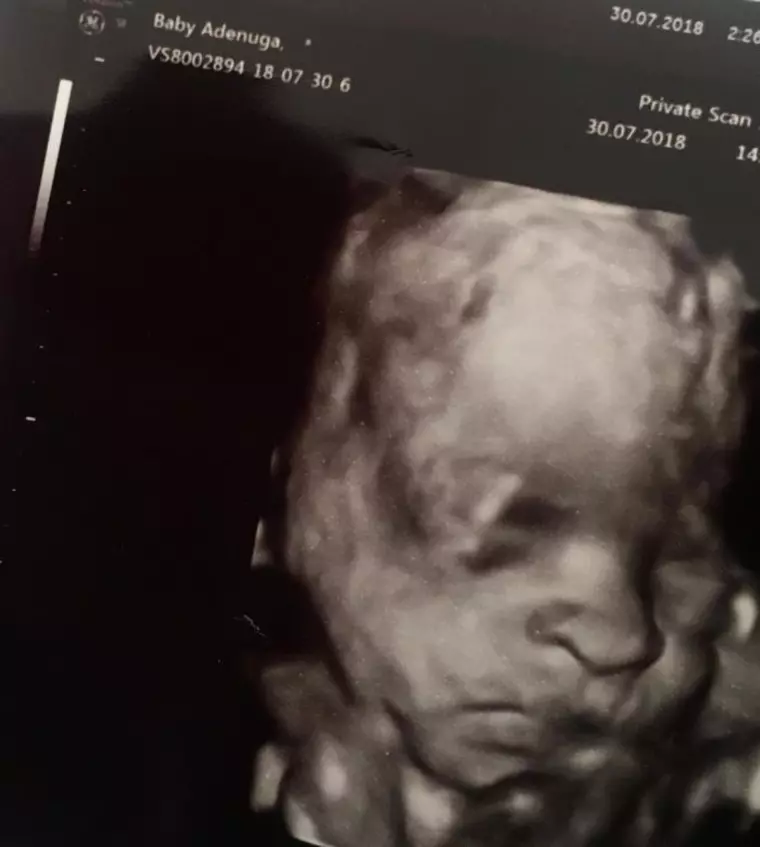

Supermodelul Naomi Campbell a creat isterie pe internet. Zvonurile au fost lansate după ce iubitul ei, rapperul Skepta în vârstă de 35 de ani a postat pe contul lui de socializare o ecografie cu un bebeluș, dezvăluind că așteaptă un copil. Rapperul a fost întotdeauna extrem de discret în legătură cu viată lui personală. Zvonuri în legătură cu relația lui și a supermodelului există încă din 2016, când au apărut împreună la British Fashion Awards.

Ecografia este realizată în 30 iulie, iar la numele pacientei scrie „baby Adenuga', semn că bebeluşul face parte din familia Adenuga (numele de familie al rapperului). Deși Naomi nu a răspuns, mai multe vedete l-au felicitat, cum ar fi Drake și Lil Yachty.